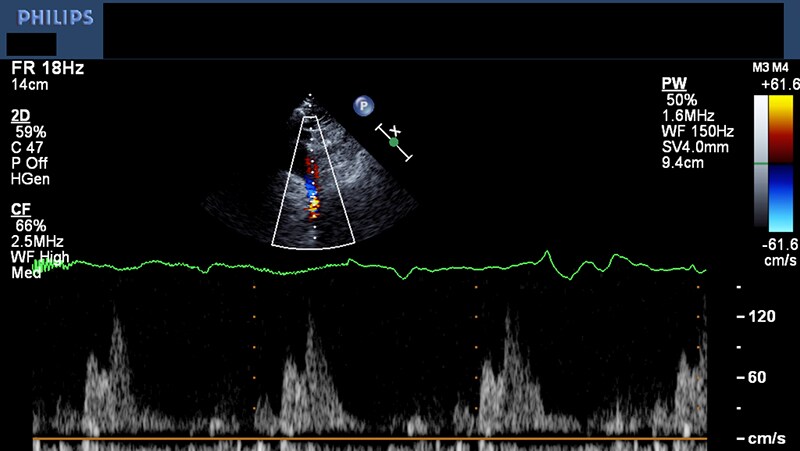

CV Imaging